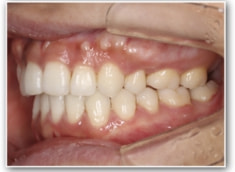

治療後